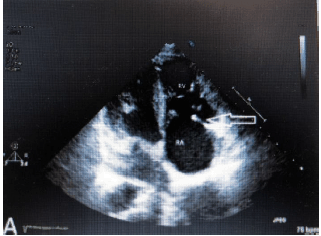

Paciente de 40 anos do sexo feminino, deu entrada na emergência referindo quadro de diarreia volumosa, confusão mental e flushing cutâneo. Relata ainda, perda de peso e intensificação dos sintomas que já duram mais de 3 meses. Ao exame físico, chamava atenção um sopro em foco tricúspide e sibilos pulmonares. Foi estabilizada e encaminhada ao laboratório de ecocardiografia que adquiriu a seguinte imagem ao exame transtorácico, compatível com achados ecocardiográficos da síndrome carcinoide.